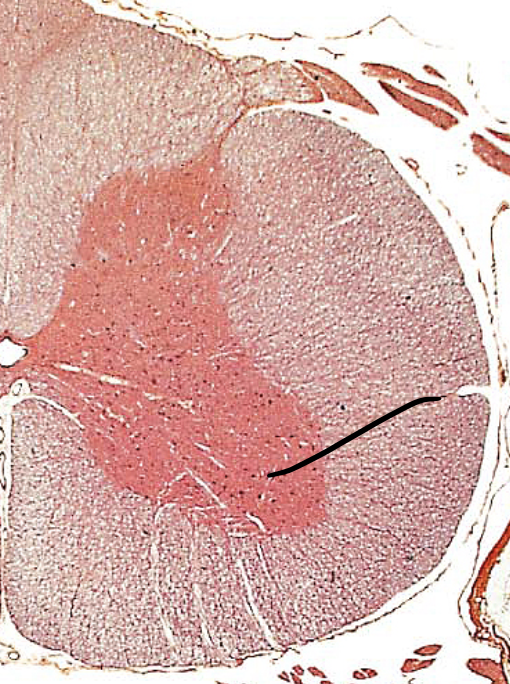

gray horns

what is the red butterfly called

anterior gray horns

floor of grey horns

lateral gray horns

middle of gray horns

posterior gray horns

ceiling of gray horns